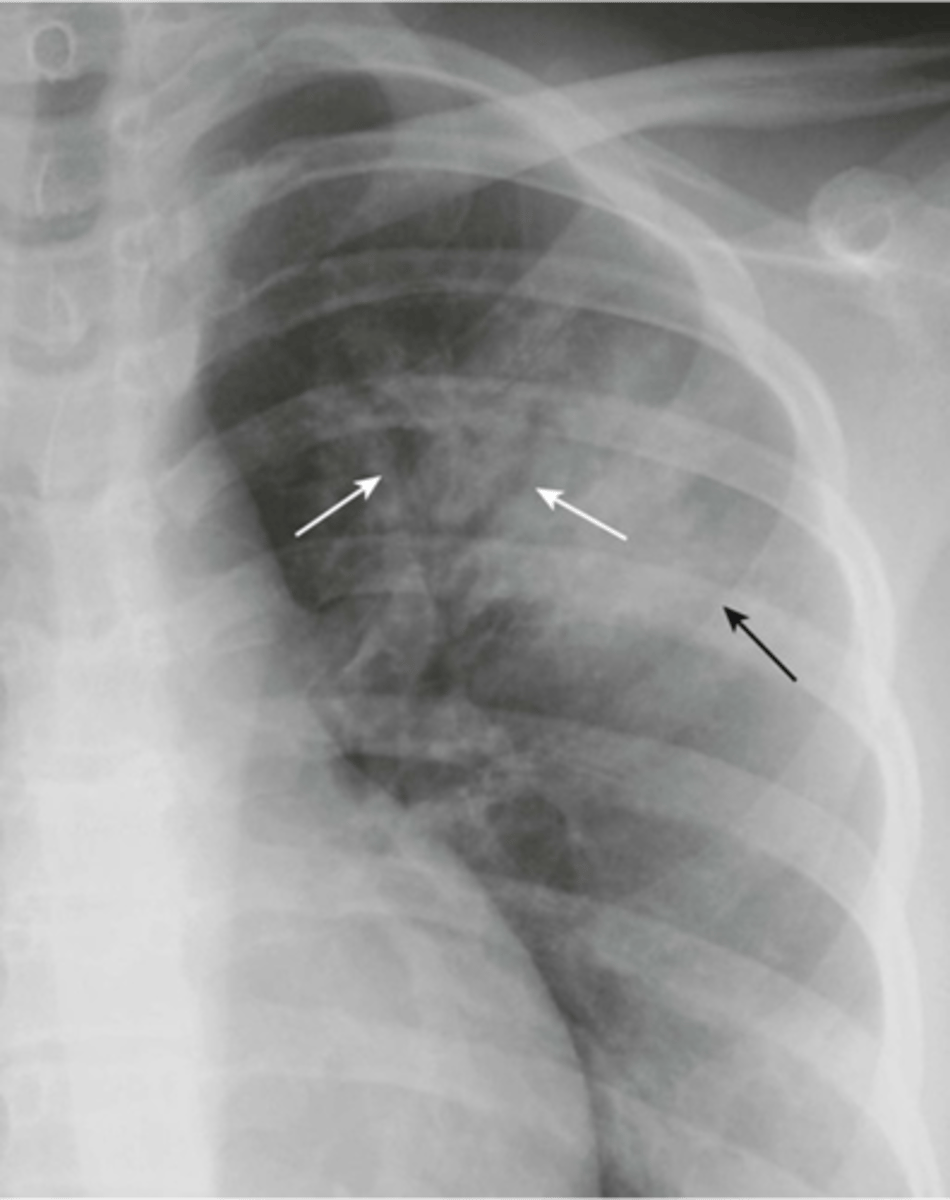

-must see visceral pleural line (expiration image is easier to see it on)

Pneumothorax appearance

-no heart or trachea shift

-subcutaneous emphysema is seen

simple pneumothorax appearance

-mediastinal and trachea shift

-almost total collapse of lung

-left diaphragm depressed

Tension pneumothorax appearance

-pneumothorax on supine radiograph

-costophrenic sulcus will appear lower on one side

Deep sulcus sign meaning